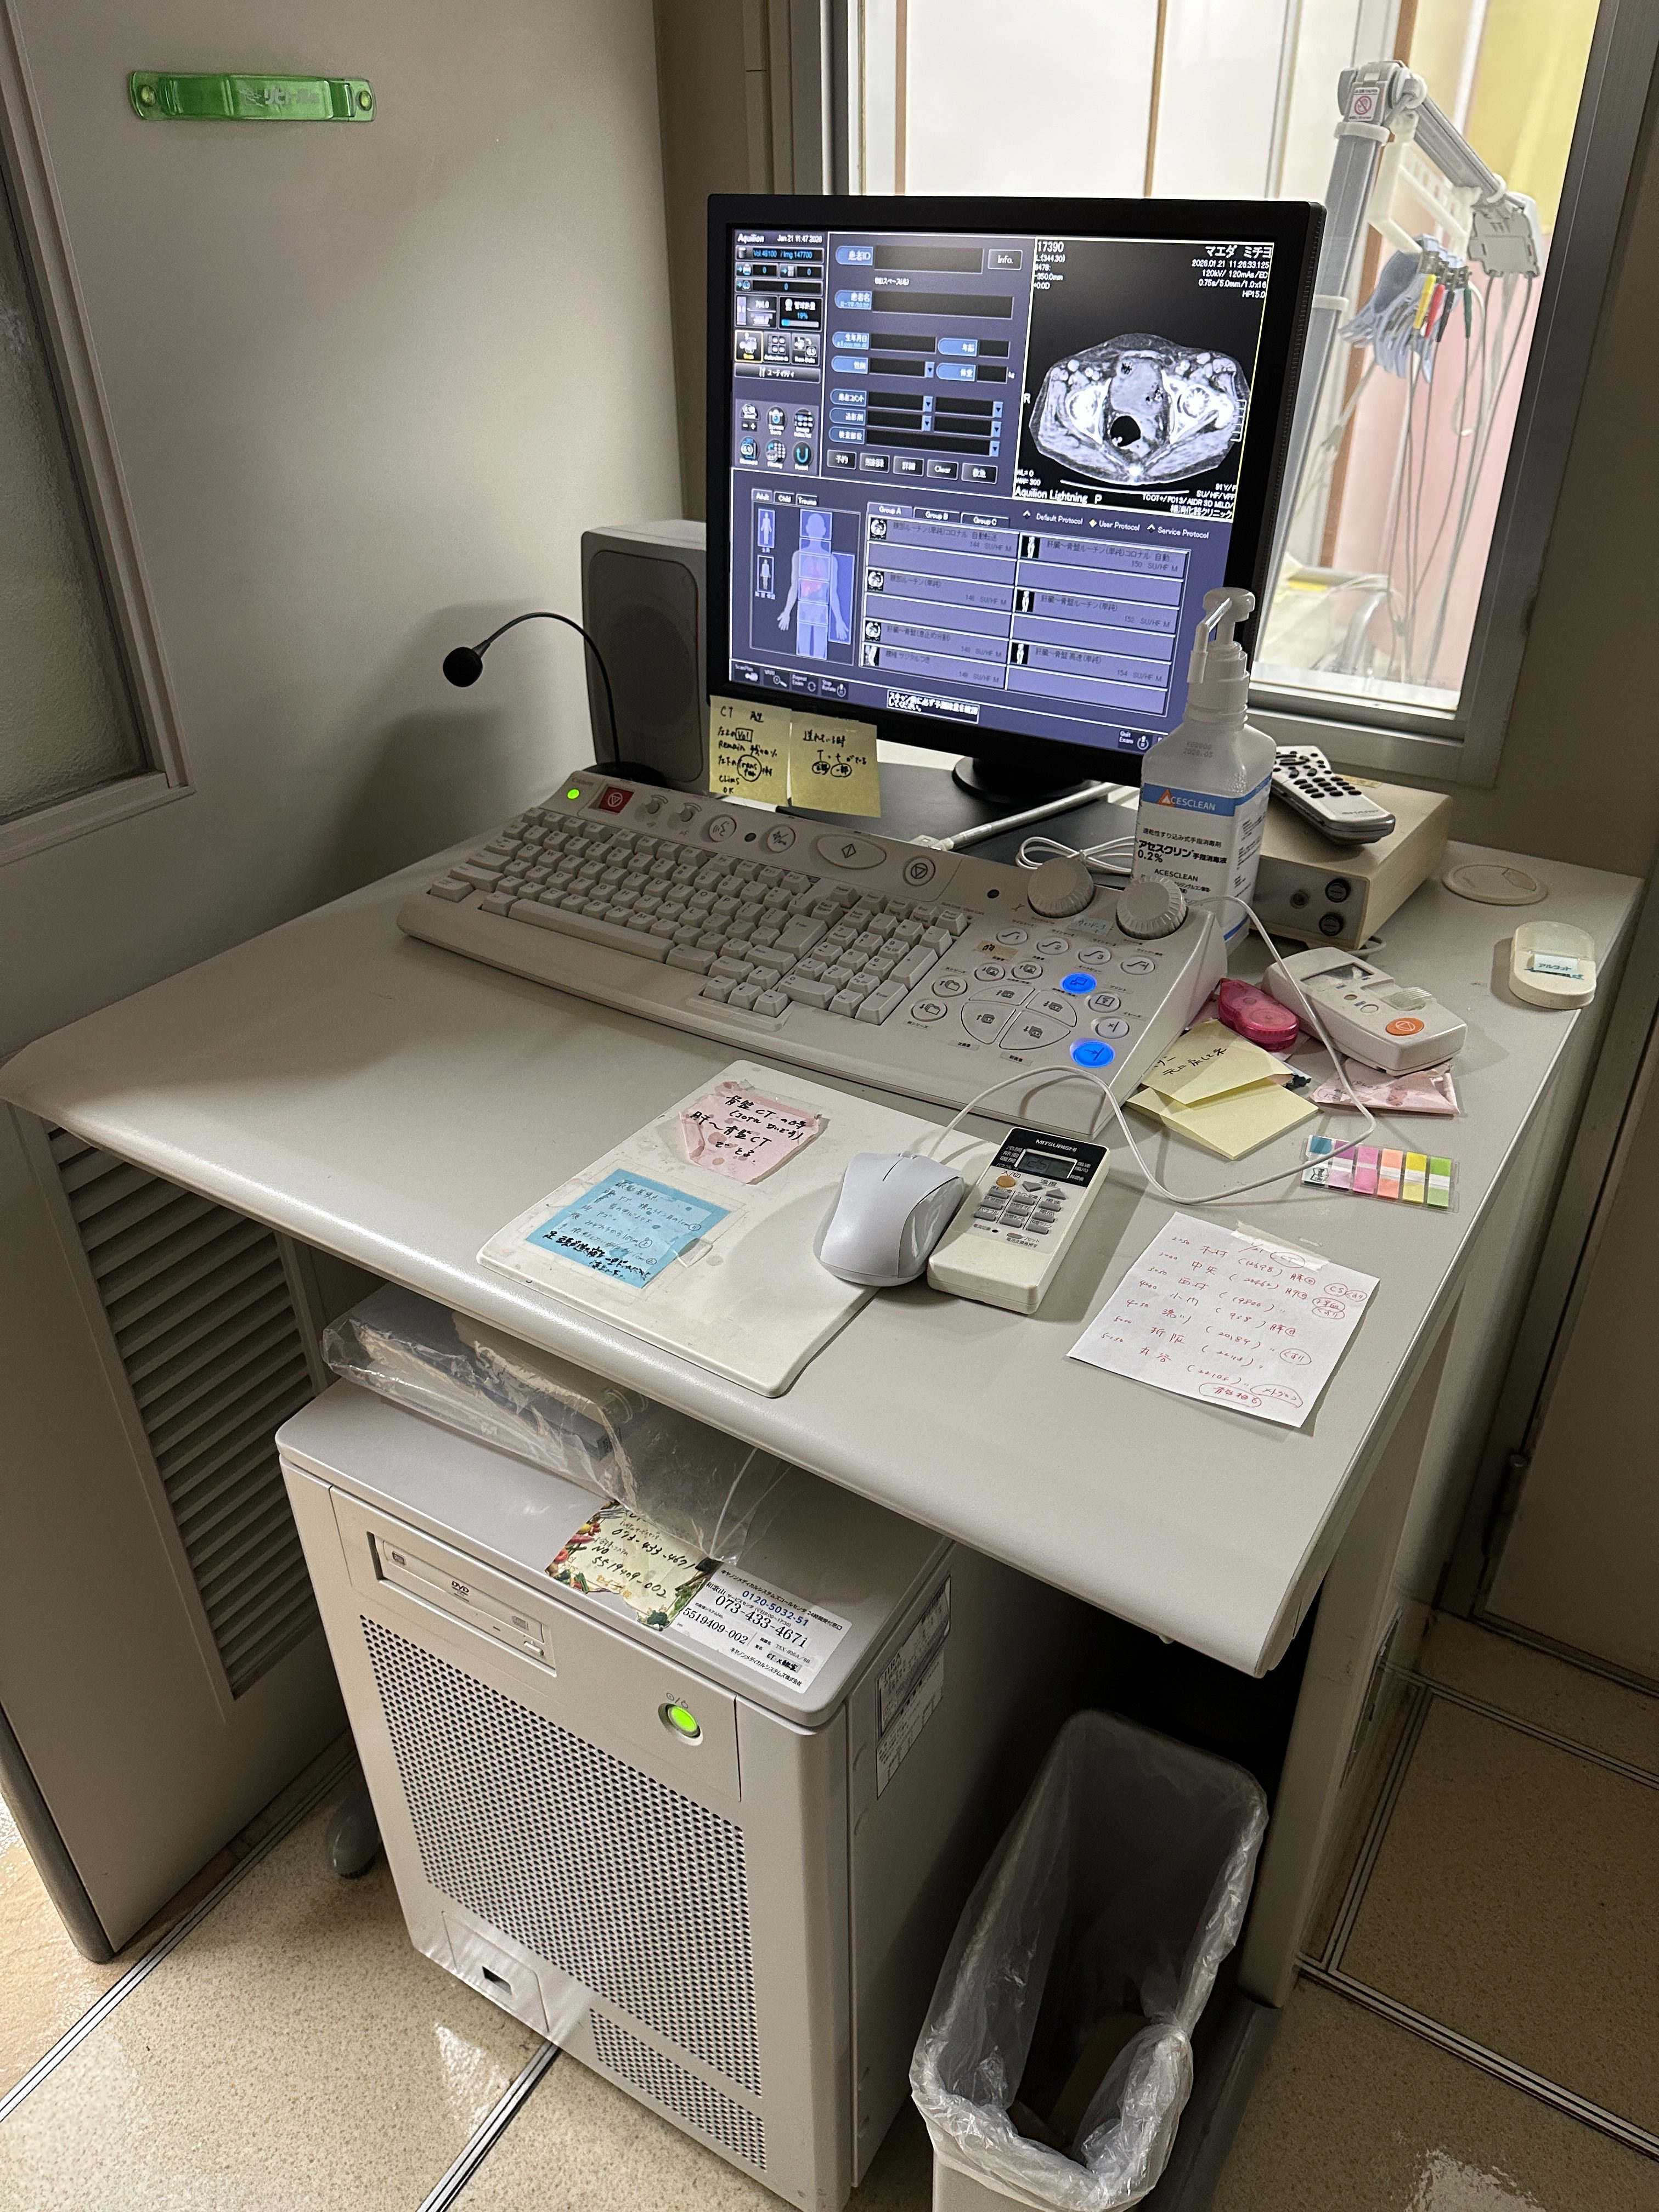

| Manufactured | : | November 2018 |

| Location | : | Japan (NEX325) |